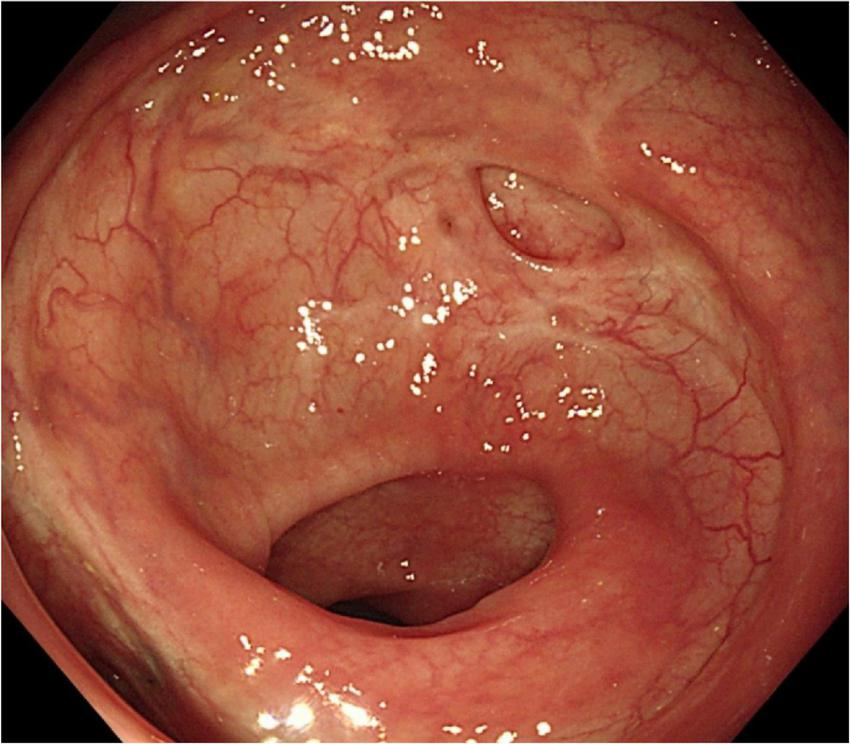

A 49-year-old woman complained of recurrent subumbilical pain without obvious inducement for half a year, and no discomfort such as bloody stool, diarrhea or constipation. The patient underwent radical resection for rectal cancer 14 years ago. The results of physical examination showed mild tenderness in the subumbilical abdomen without rebound pain. There were no significant abnormalities in routine blood parameters and related inflammatory indicators. Colonoscopy showed anastomotic diverticulum combined with stercorolith incarceration (Figure 1A). CT image of the pelvic cavity showed a mass of low density adjacent to the anastomosis (Figure 2). When the local inflammation was relieved by conservative treatment, the patient underwent endoscopic mucosal incision and lithotomy (Figures 1B,C). And the diverticulum was closed with titanium clips (Figure 1D). After 1 year of follow-up, the patient said that the abdominal pain was completely relieved, and the reexamination of colonoscopy showed that the wound healed well (Figure 3).

FIGURE 3

www.frontiersin.org

Figure 3. Endoscopic image of the scar after 1 year.

In the current case, this woman had recurrent subumbilical pain for half a year. After repeated anti-inflammatory treatment with antibiotics in other hospitals, the symptoms of abdominal pain were still repeated. When we performed colonoscopy, we found that the patient had stercorolith incarceration in the anastomotic diverticulum, which was tightly wrapped by the diverticulum and could not be removed by irrigation or biopsy forceps. We considered this should be the reason for the patient’s recurrent abdominal pain and the ineffectiveness of conservative treatment. After treated conservatively for about 3 days, the local inflammation was relieved. Then the patient underwent endoscopic mucosal incision and lithotomy, and we closed the diverticulum with titanium clips. During the follow-up 1 year after endoscopic therapy, the abdominal pain of patient was completely relieved. The reexamination of colonoscopy after 1 year also showed that the wound healed well.